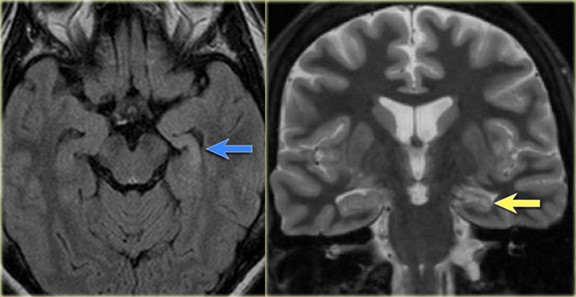

MRI 磁力共振顯示左側顳葉內側硬化症是引致癲癇的位置